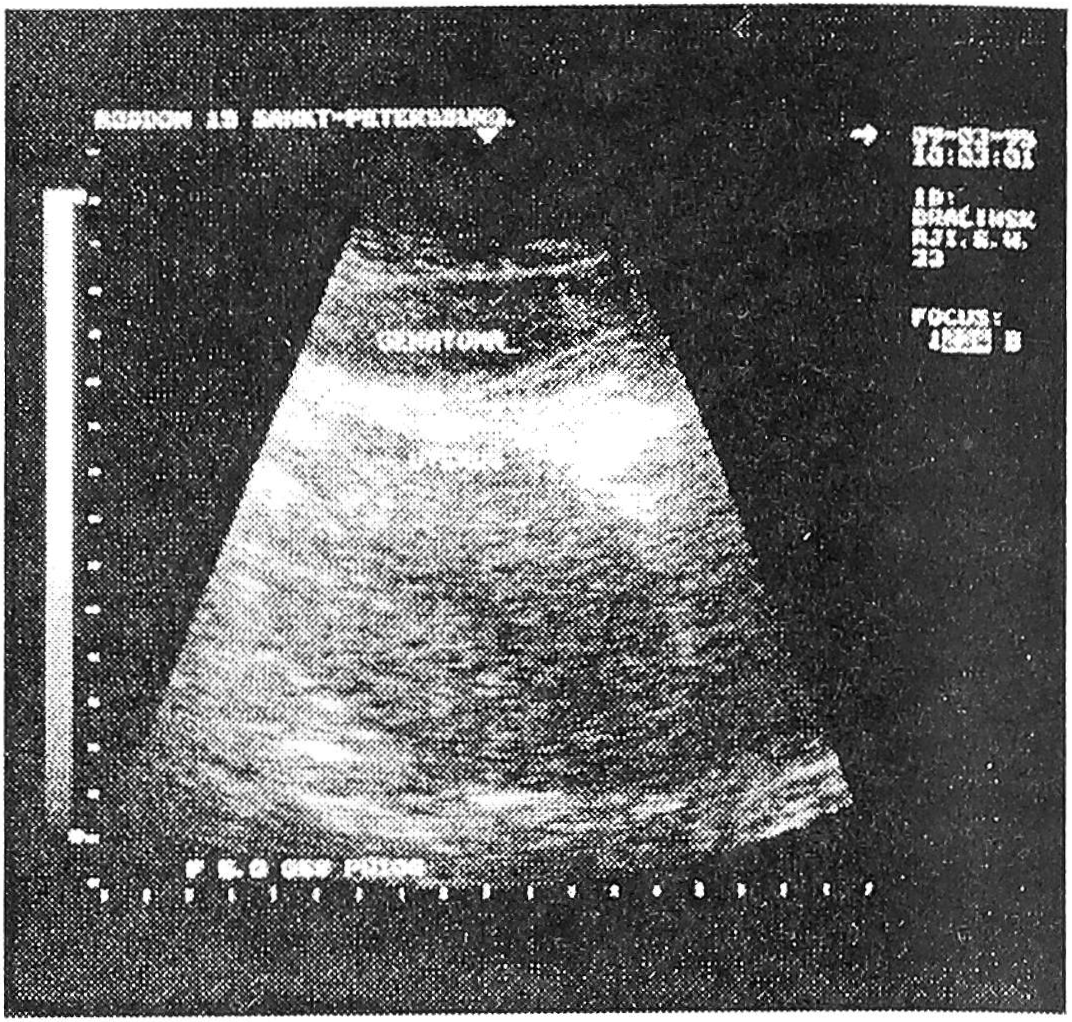

3. Матка при эндометрите (рис.2).

Рис. 2. Полость матки при эндометрите.

При ультразвуковом исследовании определяется щелевидная полость или слегка расширенная, представленная средним М-эхо средней эхогенности, не дающим акустической тени. Тонус матки снижен, размеры нормальные.